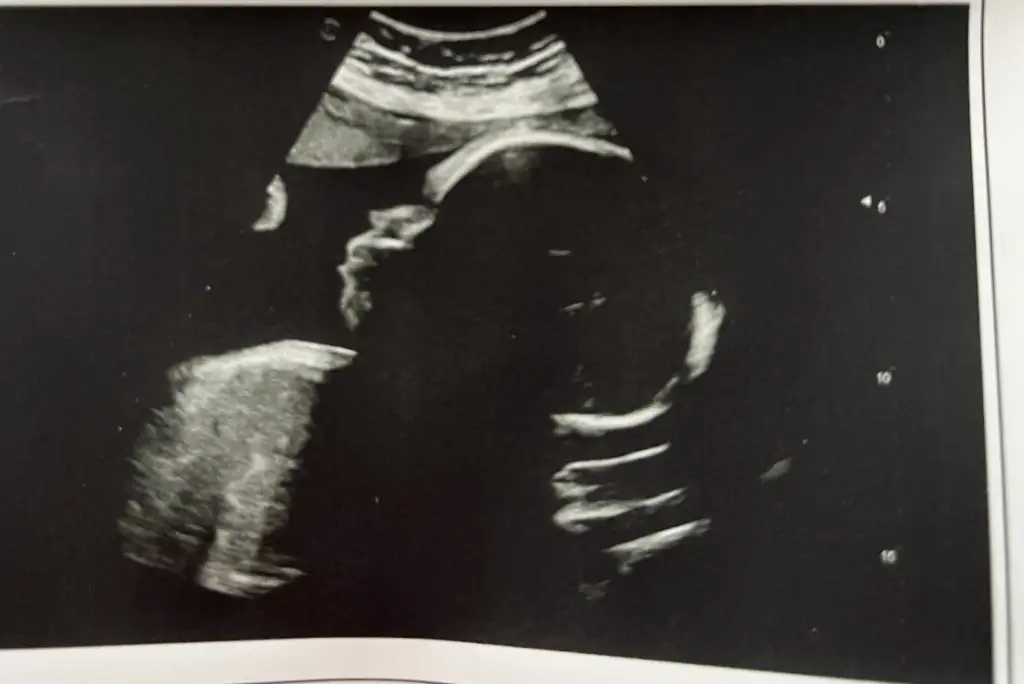

Devlet perinatolojide randevum vardı bugün (29+4). Beyindeki sıvı miktarını (sisterna magna) kontrol etti ama bugün ilk kez ölçümleri asistanına yaptırdı. Biraz artmış ama hala sınırın altında olduğu için sorun yok dedi. Artık zaten bu saatten sonra bir şey çıksa doğumdan sonra bakılır zaten dedi. Endişelensem mi bilemedim ama bundan sonra kendi doktorum dışında başka doktora gitmemeye karar verdim mecbur kalmadıkça. Asistanın ölçümlerine pek güvenemedim ama dediğine göre 1.800 kg olmuş, boyu da 39 cm. Karın çevresi önde gidiyor tabii yine bayağı. Doktorumun tatlıyı kestirdiğini söyledim. Multivitamini de kesebilirsin bence dedi. (Vitamini kes, Tatlıya tekrar başla mı demek istedi acaba) rapora da baş geliş yazmışlar (makattı en son bu pazartesi) umarım bu durumdan midemin de haberi olur.

Bu arada bugün ilk kez nst ye girdim. Zaman çok hızlı ilerliyor